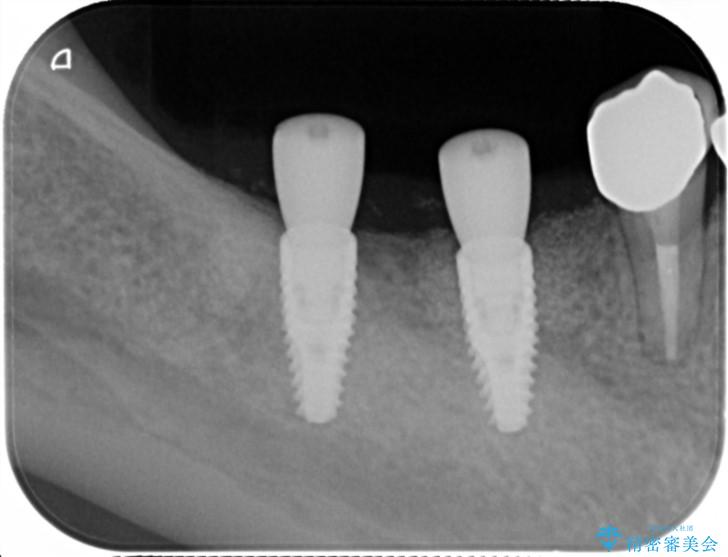

X線写真検査より、クラウンや銀歯の下で歯に大きな虫歯が発生し、抜歯を余儀なくされる状況でした。

虫歯に伴い歯槽骨の吸収も見られたので造骨後、インプラントを用いて咬合機能を回復します。

治療後

遊離歯肉移植術を伴うインプラント治療 治療後画像 遊離歯肉移植術を伴うインプラント治療 治療後画像 遊離歯肉移植術を伴うインプラント治療 治療後画像 遊離歯肉移植術を伴うインプラント治療 治療後画像